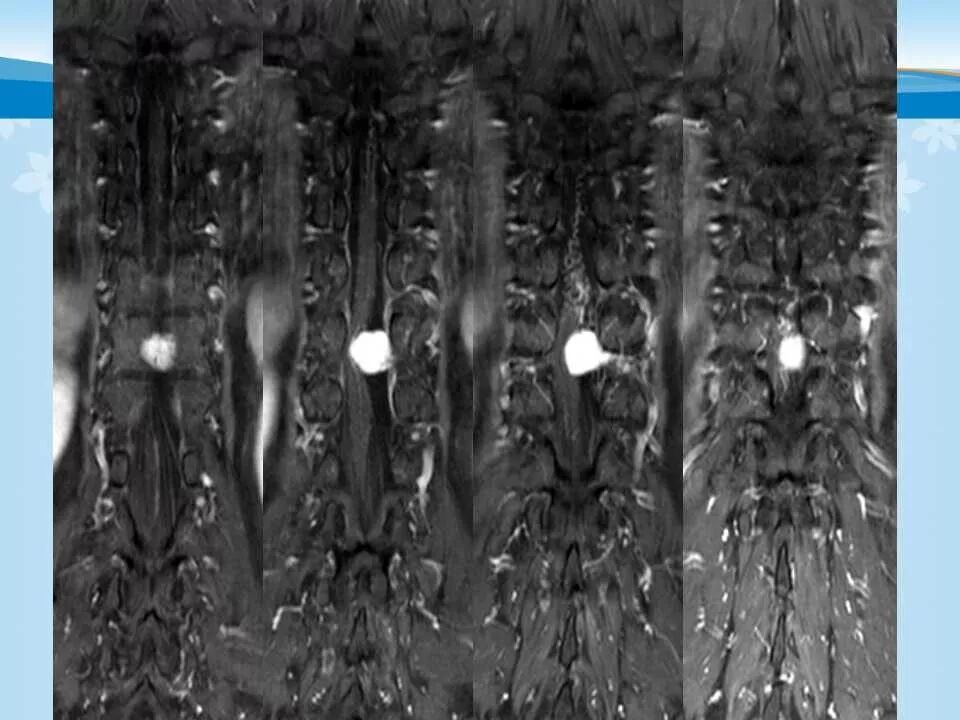

北方影像联盟 一周病例精选之“椎管占位”